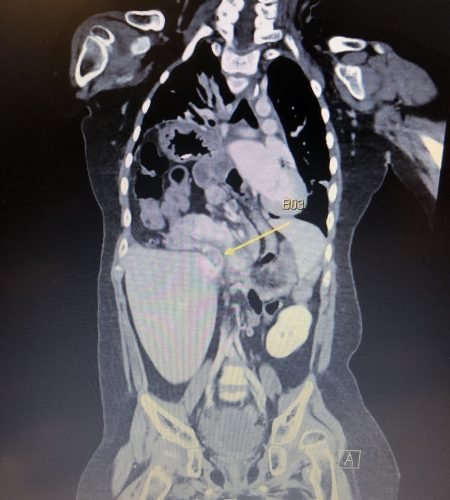

A rare type of hernia, approximately six inches in size was found in my son’s body, which had caused most of his abdominal organs to be pulled upward, exerting pressure on his lungs.

Surgery was presented as the only possible solution. However, due to the complexity and severity of the condition, the surgical team strongly advised against proceeding with the operation, warning us that there was a very high chance that my son would die on the operating table.